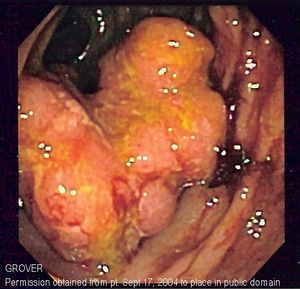

Endoscopic image of colon cancer identified in sigmoid colon on screening colonoscopy in the setting of Crohn's disease.